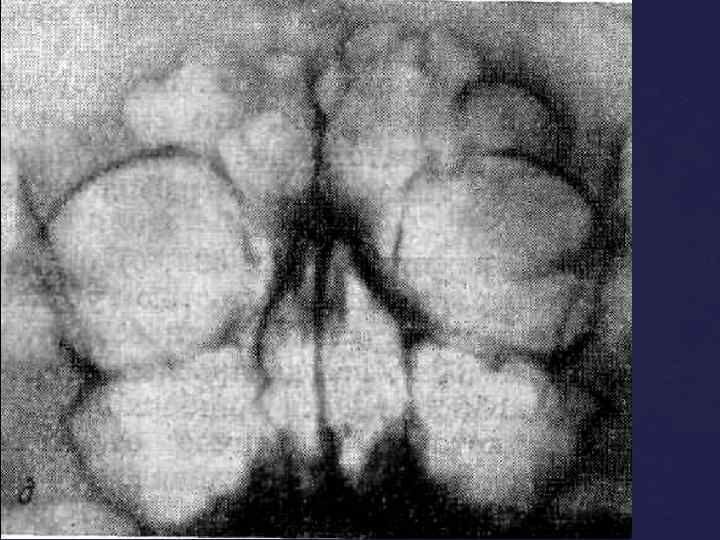

При изучении рентгенограмм черепа необходимо учитывать следующие моменты: 1)Наиболее интенсивную тень дают плотные участки костей (каменистая часть височной кости, скуловая кость). 2) Глазница и воздухоносные полости выглядят как просветления. В боковой проекции хорошо видно турецкое седло. По его размерам и степени сохранности судят о величине гипофиза. Изучение R-гр. черепа

При изучении рентгенограмм черепа необходимо учитывать следующие моменты: 1)Наиболее интенсивную тень дают плотные участки костей (каменистая часть височной кости, скуловая кость). 2) Глазница и воздухоносные полости выглядят как просветления. В боковой проекции хорошо видно турецкое седло. По его размерам и степени сохранности судят о величине гипофиза. Изучение R-гр. черепа